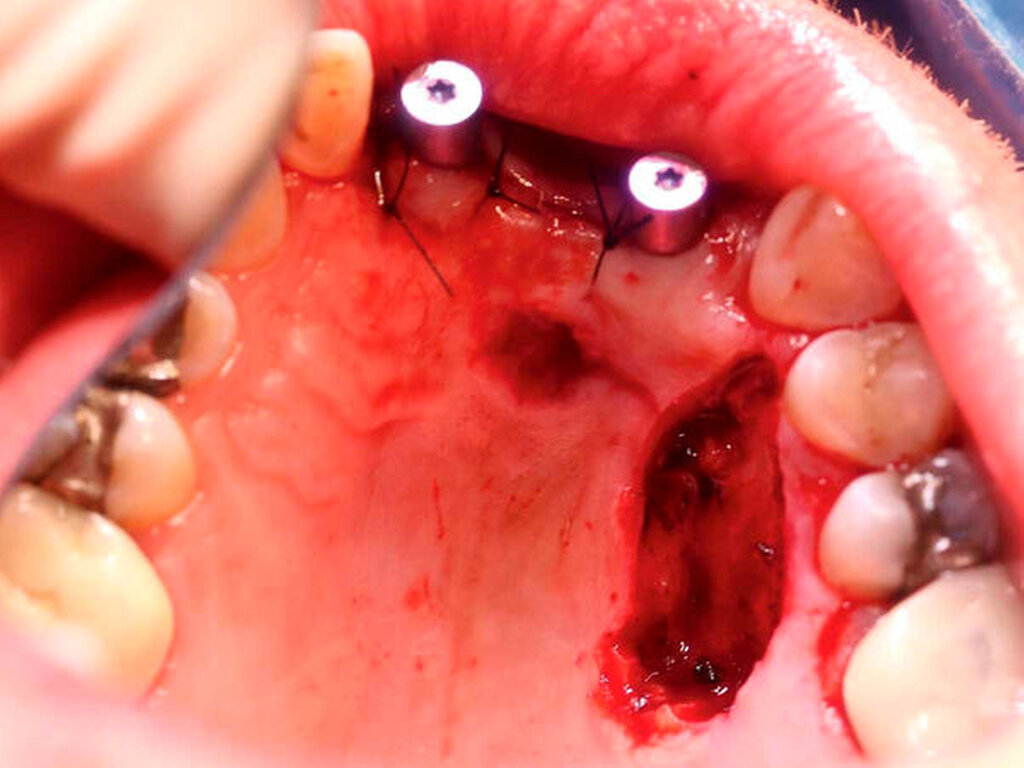

Anschließend wurde zur Ausbreitungsdiagnostik eine Magnetresonanztomografie (MRT) der Kopf-Hals-Weichteile mit Kontrastmittel durchgeführt (Abbildung 2). Hierbei kam eine malignomsuspekte Raumforderung im Oberkiefer im Bereich der regiones 11 bis 21 zur Darstellung, metastasensuspekte Auffälligkeiten der Halslymphknoten konnten nicht ausgemacht werden. Nach Besprechung des Falles in der interdisziplinären Tumorkonferenz wurde der Befund lokal mit Sicherheitsabstand in toto exzidiert und die mit der Raumforderung kommunizierenden Zähne 12, 11 und 21 extrahiert (Abbildung 3).

Nach sekundärer Granulation der Exzisionswunde erfolgte die Insertion von zwei Implantaten in den regiones 12 und 21 (Abbildung 5). Da eine zeitnahe Radiatio im weiteren Verlauf nicht ausgeschlossen werden konnte, wurde auf eine Augmentation des zuvor teilresezierten Alveolarkamms verzichtet, um eine festsitzende Implantatversorgung nicht zu gefährden. Weitere sechs Monate später trat erneut ein Rezidiv im Bereich des harten Gaumens auf (Abbildung 6), das wiederum ausgedehnt im Sinne einer R0-Situation exzidiert wurde. Zusätzlich wurden die zuvor inserierten Implantate im gleichen Eingriff freigelegt (Abbildung 7).